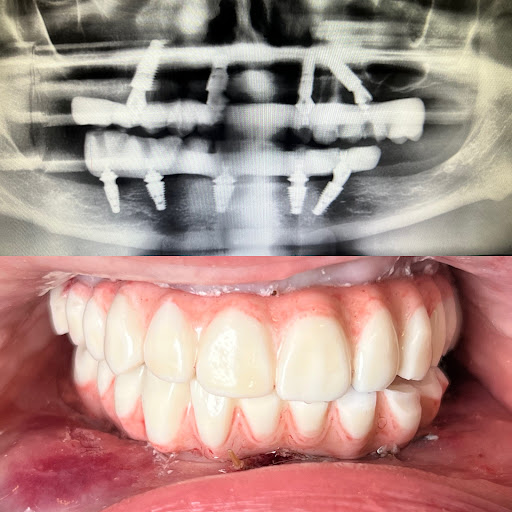

Signature Smiles Family Dentistry

Photos